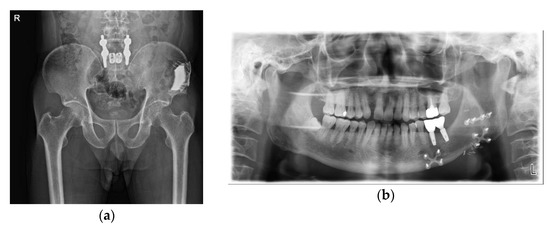

2.1. Case 1: SCC on Right Mandibular Buccal Mucosa

2.2. Case 2: Ameloblastoma on Left Mandibular Body and Angle

2.3. Case 3: Verrucous Carcinoma on Right Upper Gingiva